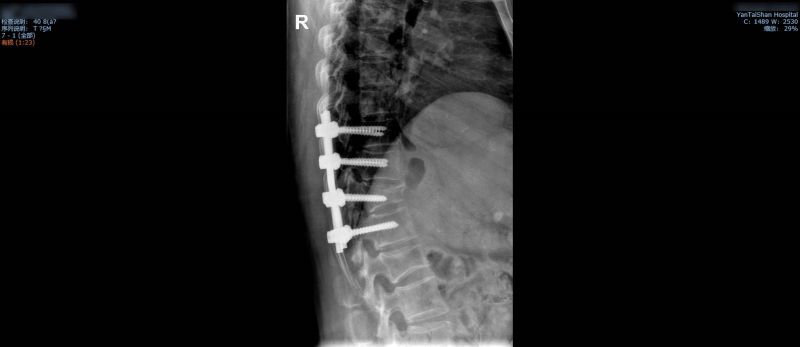

有了充分的术前准备,当天的手术在4小时之内完成,术中的出血量非常小,患者4个节段的胸椎管得以减压固定。术后第4天,她就可以下地活动。在此期间,病房护理人员也给予王阿姨无微不至的关怀,确保了术后安全,并帮她得以早日康复。